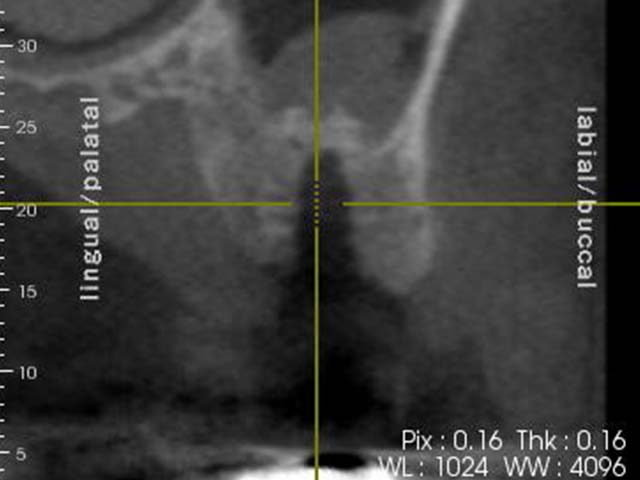

鼻竇增高術(垂直)+植牙 首頁 案例分享 人工植牙 鼻竇增高術(垂直)+植牙 鼻竇增高術(垂直)+植牙 術前評估 PRF(使用法國離心機,萃取出有益於傷口癒合的血小板,並加以濃縮) 鼻竇增高術 從植牙傷口置入萃取的PRF,將鼻竇往上抬升,再植入骨粉,以利植牙。 電腦斷層—術前,術中,假牙完成